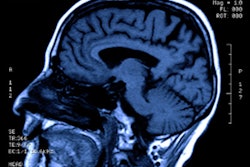

Functional MRI images show that parts of the brains of obese children show differences compared with their normal-weight or overweight counterparts, according to a study published April 16 in Cerebral Cortex.

Pujol's team analyzed fMRI images of 230 children between the ages of eight and 12, finding that in obese children, two areas of the brain -- the orbitofrontal cortex and the amygdala, both of which regulate sensations of reward and punishment and the relationship to the part of the brain that regulates basic needs -- were "altered and hyperexcited" compared with those same regions in healthy-weight or overweight children.